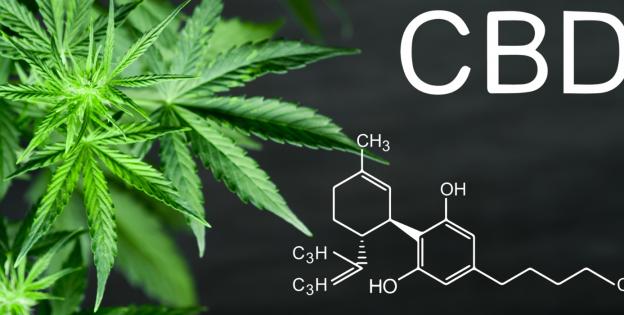

A Study Confirms that the CBD in Cannabis Kills Malignant Breast Cancer Cells

Spanish researchers take the first steps to create marihuana without THC but retaining its therapeutic powers

CBD extract can reduce seizures in epileptic children by up to 50%

Spanish Researchers Discover How to Alleviate Chronic Pain by Combining Cannabinoids and Nanotechnology